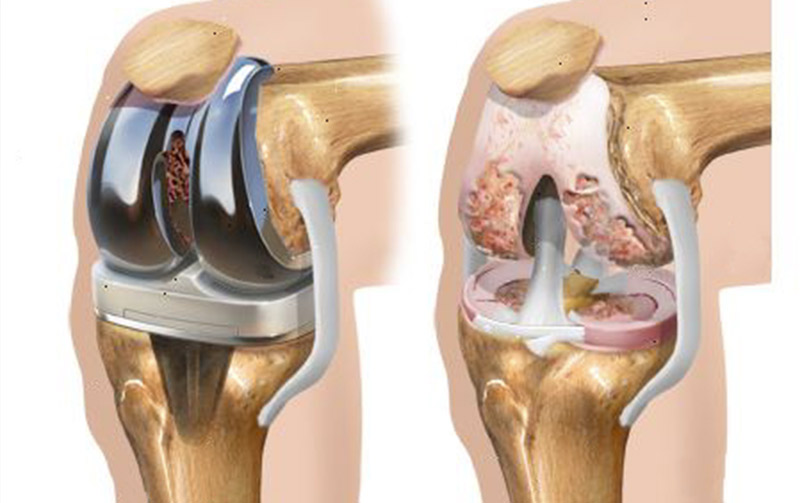

L’intervento consiste nel sostituire l’articolazione artrosica (malata) con una artificiale, creando nuove superfici di contatto e scivolamento tra le ossa del femore e della gamba.

L’intervento è eseguito in anestesia locoregionale o generale; il tipo di anestesia più indicato al Suo caso, tuttavia, sarà scelto dall’anestesista che Le fornirà tutte le informazioni utili in merito. L'intervento richiede di un laccio applicato alla coscia per evitare sanguinamenti eccessivi e di un’incisione sulla parte anteriore del ginocchio con esposizione dell’articolazione. Con appositi strumenti viene tagliata e preparata la superficie del femore e della tibia e quando necessario anche della rotula, asportando le superfici articolari danneggiate. Esse vengono ricoperte con elementi in metallo (cromo-cobalto e/o titanio e/o metallo ceramizzato) che si articolano tra di loro tramite un inserto (posizionato tra le superfici metalliche) in materiale plastico, chiamato polietilene. In genere le componenti metalliche vengono fissate all’osso con resine a presa rapida (cemento). Alcuni tipi di impianto possono essere applicati all’osso senza cemento (raramente). Segue la ricostruzione dei piani anatomici e la sutura di sottocute e cute. Può essere necessario il posizionamento di un drenaggio. Dopo l’intervento potrebbe essere necessario eseguire delle trasfusioni di sangue.